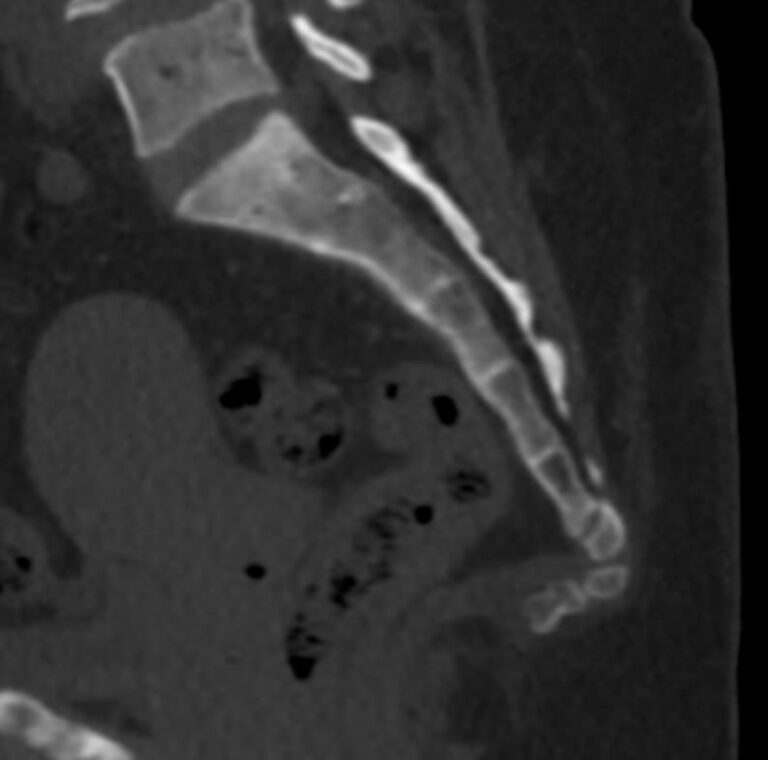

Одним из наиболее информативных методов диагностики заболеваний копчика является мультиспиральная компьютерная томография. Метод основан на использовании рентгеновского излучения и применения инновационных компьютерных программ для детальной визуализации состояния органов и систем организма. Процедура отличается быстротой, безболезненностью и неинвазивностью (то есть проводится без нарушения целостности кожи и расположенных под ней тканей).

Инновационные возможности аппаратов дают возможность получить множество послойных снимков высокого качества и реконструировать на их основе трехмерную модель органа. Кроме того, аппаратура позволяет за счет сокращения времени сканирования максимально уменьшить лучевую нагрузку на пациента.

Что покажет КТ копчика

- перелом крестца или копчика, смещение позвонков и другие травмы, в том числе застарелые.

- кисты копчика.